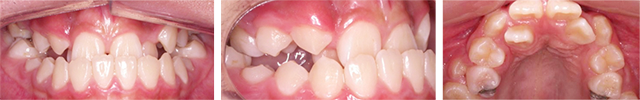

치열이 고르지 않고 좌측 송곳니가 나오지 않아 검진을 위해 내원한 학생. 방사선 사진 촬영 결과 인접 치아 뿌리 끝에 매복되어 있는 송곳니를 발견하였으며 발치를 고려하였으나 성장기 동안 앞니가 없이 지내야 하고 어린 나이에 적절한 보철 치료를 하기 어려워 치아를 살리는 계획을 수립. 구강외과 협진으로 수술을 통해 매복치아에 장치를 부착 후 견인 및 배열하였습니다.

총 2회에 걸친 구강외과와의 협진으로 매복된 송곳니에 장치 부착하여 제자리로 이동시켰습니다. 치료 결과 고르지 않던 치열이 자연스러운 형태로 교정이 완료 되었습니다.